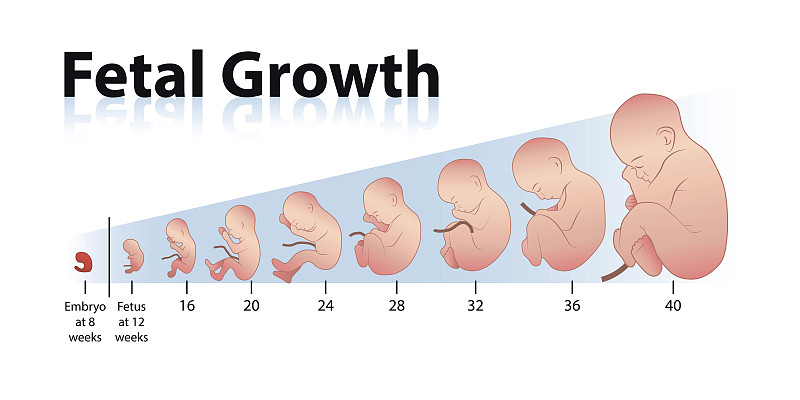

胎儿生长详情

EPS